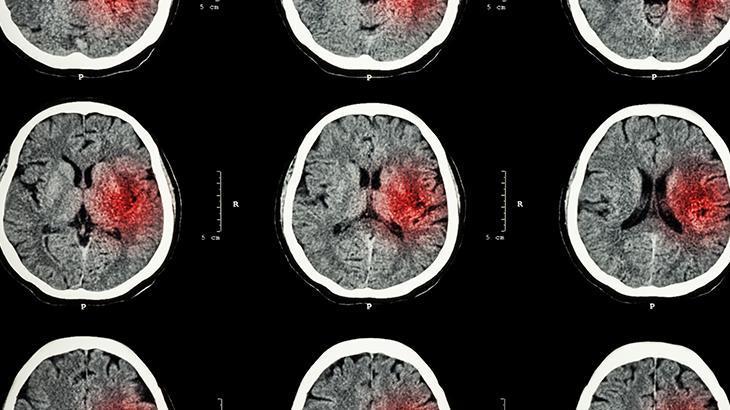

“İnme, klinik bir tablo. Bu klinik tabloya yol açan şeyse ya beyin damarlarındaki bir embolinin yani pıhtının yol açtığı tıkanma sonucu oluşan, beynin kanlanmasının bozulması ya da bazen kanama ile ortaya çıkabilen bir durum. Bilinç değişikliği, bir tarafta güçsüzlük, uyuşukluk, bazen nöbetlerle birlikte de bize gelebiliyor hastalar. Konuşma bozukluğu, anlama bozukluğu, görmenin ani olarak tek taraflı kaybolması şeklinde ortaya çıkabiliyor belirtiler. Çok çeşitli semptomları olduğu için ve hastalarımız da bazen sadece tek taraflı güçsüzlük durumunu inme olarak kabul edip diğer semptomları gözden kaçırabiliyor ve hastaneye gidişler gecikebiliyor.